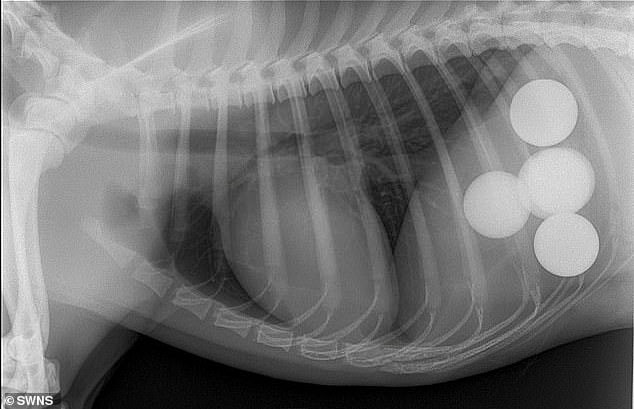

Lisa conta ao Daily Mail que também já encontrou preservativos e até um vibrador dentro de um cão. Na foto é um raio-x de um cachorro Louis Springer Spaniel que engoliu bolas de golfe.